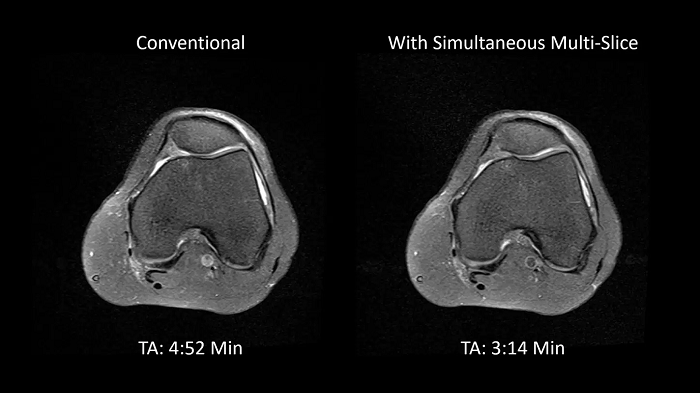

Simultaneous Multi-Slice

Siemen Healthineers’ Simultaneous Multi-Slice TSE is an exclusive approach to accelerate data acquisition in TSE imaging. By getting multiple slices simultaneously, users can save a maximum of 50% scan time, thereby reducing motion artifacts, minimizing patient slot times, and maintaining patients friendliness.

Image Courtesy: University Hospital Erlangen, Germany | Image-ID: 4aaaa0375

PD TSE FatSat with SMS

In MSK imaging, TSE is the workhorse. Using the Siemens Healthineers dedicated SMS TSE technique, users can stay on top of measurement times without compromising on image quality while resolving orthopedic clinical concerns.

TA = 3:46 minutes

Image Courtesy: University Hospital Erlangen, Germany | Image-ID: 4aaaa0449